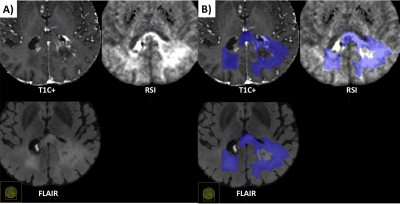

An example of segmentation for a cellular non-enhancing tumor case is shown in Fig 1. While the regions of FLAIR hyperintensity in the splenium of the corpus callosum and bilateral parieto-occipital white matter did not demonstrate significant enhancement, they showed increased RSI cellularity signal compatible with cellular infiltrative tumor (Fig 1A). These regions were segmented as tumor tissue in Fig 1B. An example of segmentation for a case with only post-treatment changes is shown in Fig. 2. The red arrow in Fig 2A demonstrated peripheral nodular enhancement at the anterior margin of the surgical cavity but the RSI cellularity map (blue arrow) did not demonstrate RSI cellularity signal in the enhancing regions or surrounding edematous tissue, suggesting post-treatment changes rather than recurrent tumor. This was confirmed on the follow-up scan (Fig 2B) where this region of nodular enhancement improved (green arrow) and tissue necrosis increased (yellow arrow) as shown by the very high RSI signal. Tumor segmentations with several variations of the Deep Learning model with different inputs are shown in Fig 3 for an individual test subject and the average Dice scores over the entire testing set is shown in Table 1. Adding RSI cellularity to the combination of T1 pre, T1C+ and FLAIR sequences increased the Dice score from 0.50 to 0.65. Although adding ADC to T1, T1C+, and FLAIR sequences also increased the Dice score, the increase was less pronounced than with RSI (0.60 ± 0.31 vs. 0.65 ± 0.24)." Fig 4 demonstrates an inverse relationship between volume of enhancing cellular tumor (both T1C+ and RSI positive) and the overall survival for patients with RSI scans within 180 days following surgical resection (n=20).

Fig. 1. Example of segmentation for a cellular non-enhancing tumor case. A) MRI volumes. While the hyper FLAIR signal regions in the splenium of the corpus callosum and bilateral parieto-occipital white matter did not demonstrated enhancement, they showed increased RSI signal demonstrating residual tumor. B) These regions were included in manual segmentations of cellular tumor.